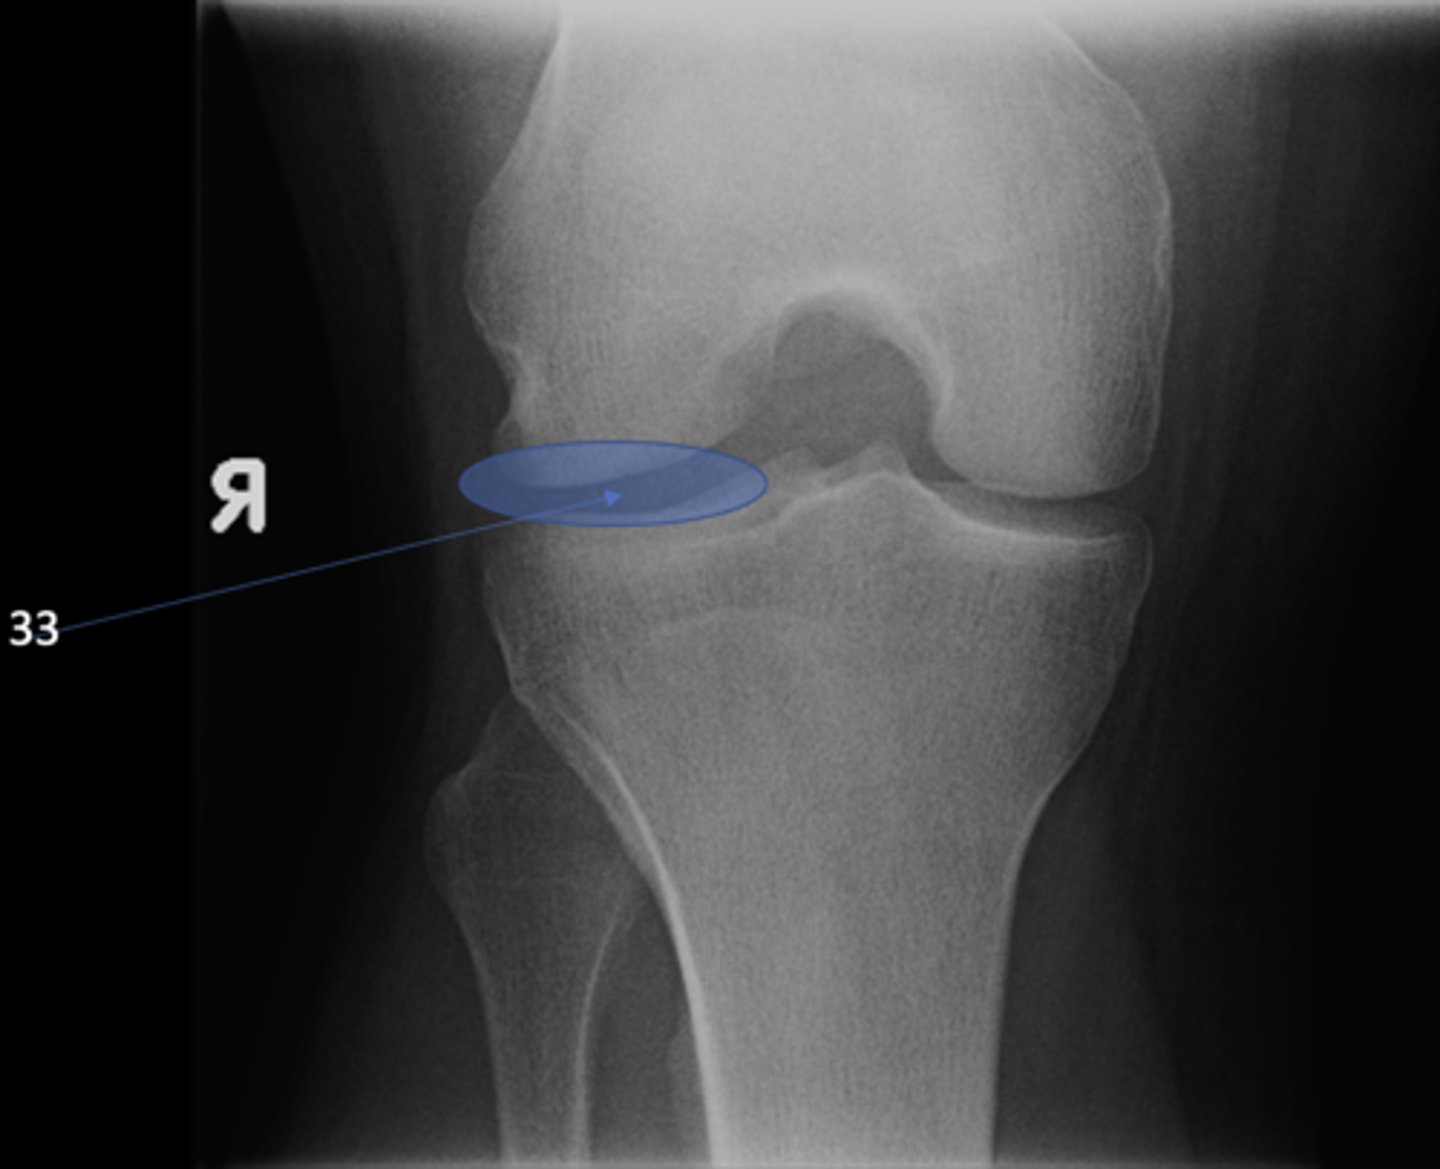

Lateral tibiofemoral joint

ID 33 (joint)

<p>ID 33 (joint)</p>